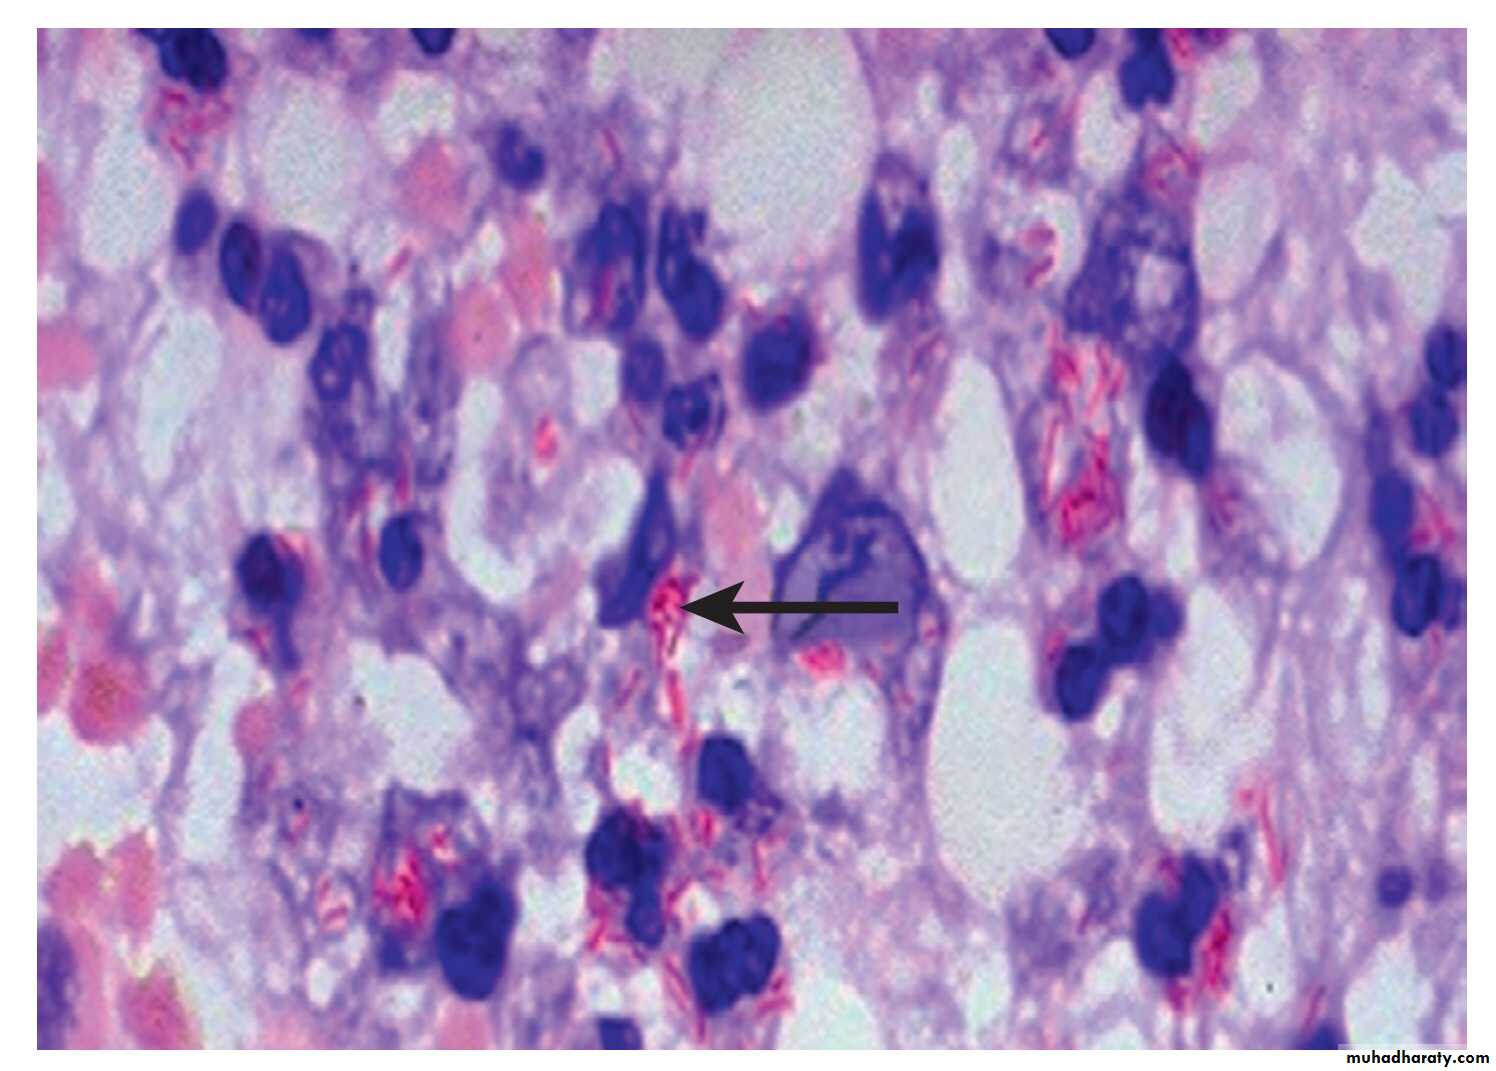

Tuberculous bacilli are difficult to stain.

The most effective techniques are the Ziehl–Neelsen and rhodamine–auramine.

Positive Ziehl–Neelsen stain. Mycobacteria retain the red carbol fuchsin stain, despite washing with acid and alcohol